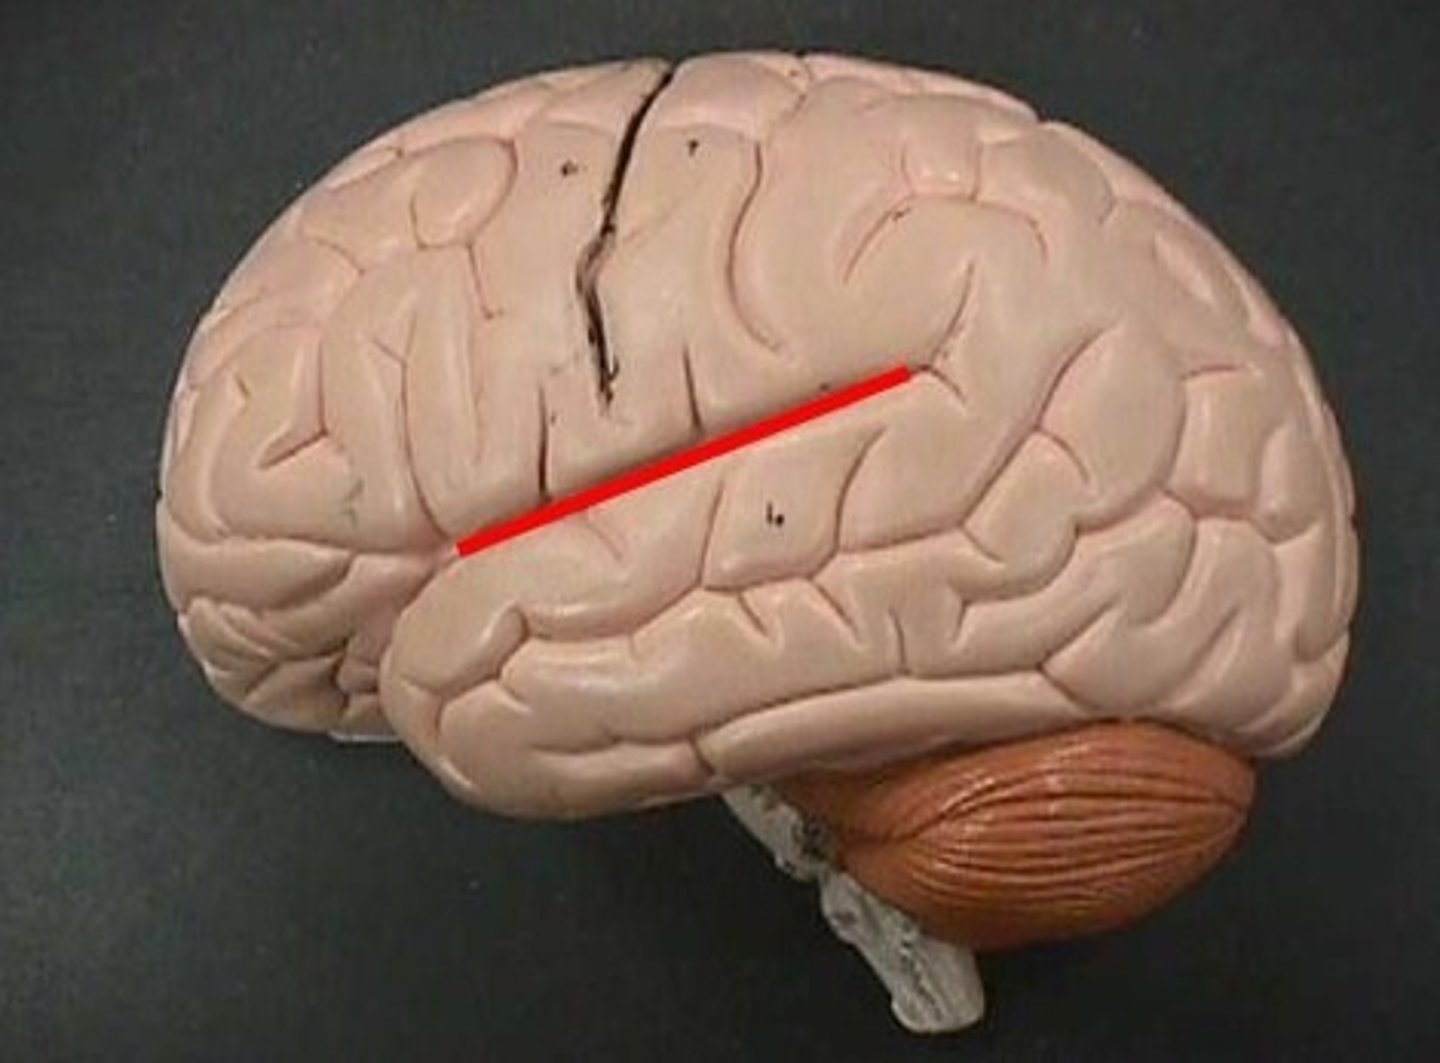

lateral cerebral sulcus

separates the frontal lobe from the temporal lobe